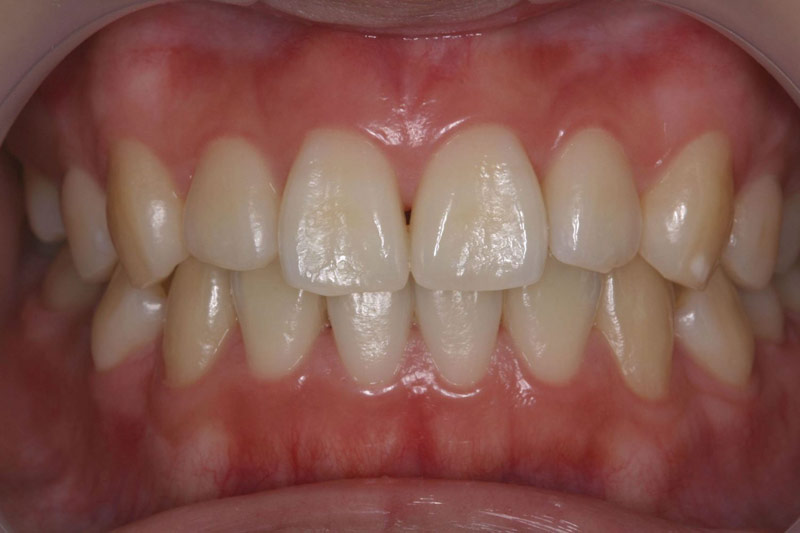

定期健診を継続し、虫歯に一回もなったことのない歯並びのきれいな患者さんが多く育っています。

子供達を健康で綺麗な歯並びの永久歯列に誘導していくことを咬合育成と言います。開業時から来院していた子供達を見ていて、どうしたら綺麗な歯並びにできるのかを研究してきました。最近その成果が上がるようになり多くの子供達が健康できれいな歯並びをもった大人になって来院するようになっています。対外的にも「講演・論文」のページにあるように各地の歯科大学や歯科医師会からその分野の講演を依頼されるようになり、いつのまにか須貝歯科医院の得意分野になってしまいました。永久歯への生え替わりの時期が最も重要な時期です。簡単な装置で歯並びを改善していくのですが患者さんによっては矯正専門医に紹介しなければならないケースもあります。その時は地元の信頼できる矯正専門医をご紹介しています。

上の前歯は下の前歯より前にないといけませんが、前歯の生え替わりの時に1本逆に生えてきました。そのままではきれいな歯並びにはなりそうもありません。この時が治療のタイミングです。簡単な矯正装置で改善しただけでその後きれいな永久歯列になりました。